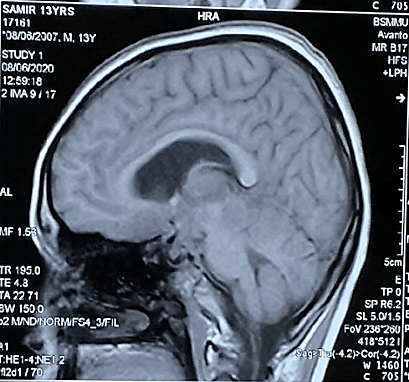

Figure 2: On T1-weighted images showed multiple ill-defined mixed iso to slight hypointensity lesions.

On the MRI T1-weighted images, multiple ill-defined mixed iso to slight hypointensity lesions were found to be located in basal, suprasellar, interpeduncular, prepontine, ambient and quadrigeminal cisterns (Figure 2) and the lesions became heterogeneously hyperintense on T2 WI (Figures 3A & 3B). The lesions were also hyperintense in FLAIR images (Figure 4) and after contract enhancement, there were multiple conglomerate ring shaped tuberculomas of 0.5 to 1cm size located at the basal, suprasellar and perimesencephalic cisterns and along the leptomeninges of basal region of cerebral hemisphere with racemose patterns. The central nonenhancing portions corresponded to caseation necrosis (Figures 5A & 5B). After treatment with antitubercular chemotherapy for 18 months the patient showed complete clinical recovery (Figure 6) but persisting radiological features of tuberculosis.